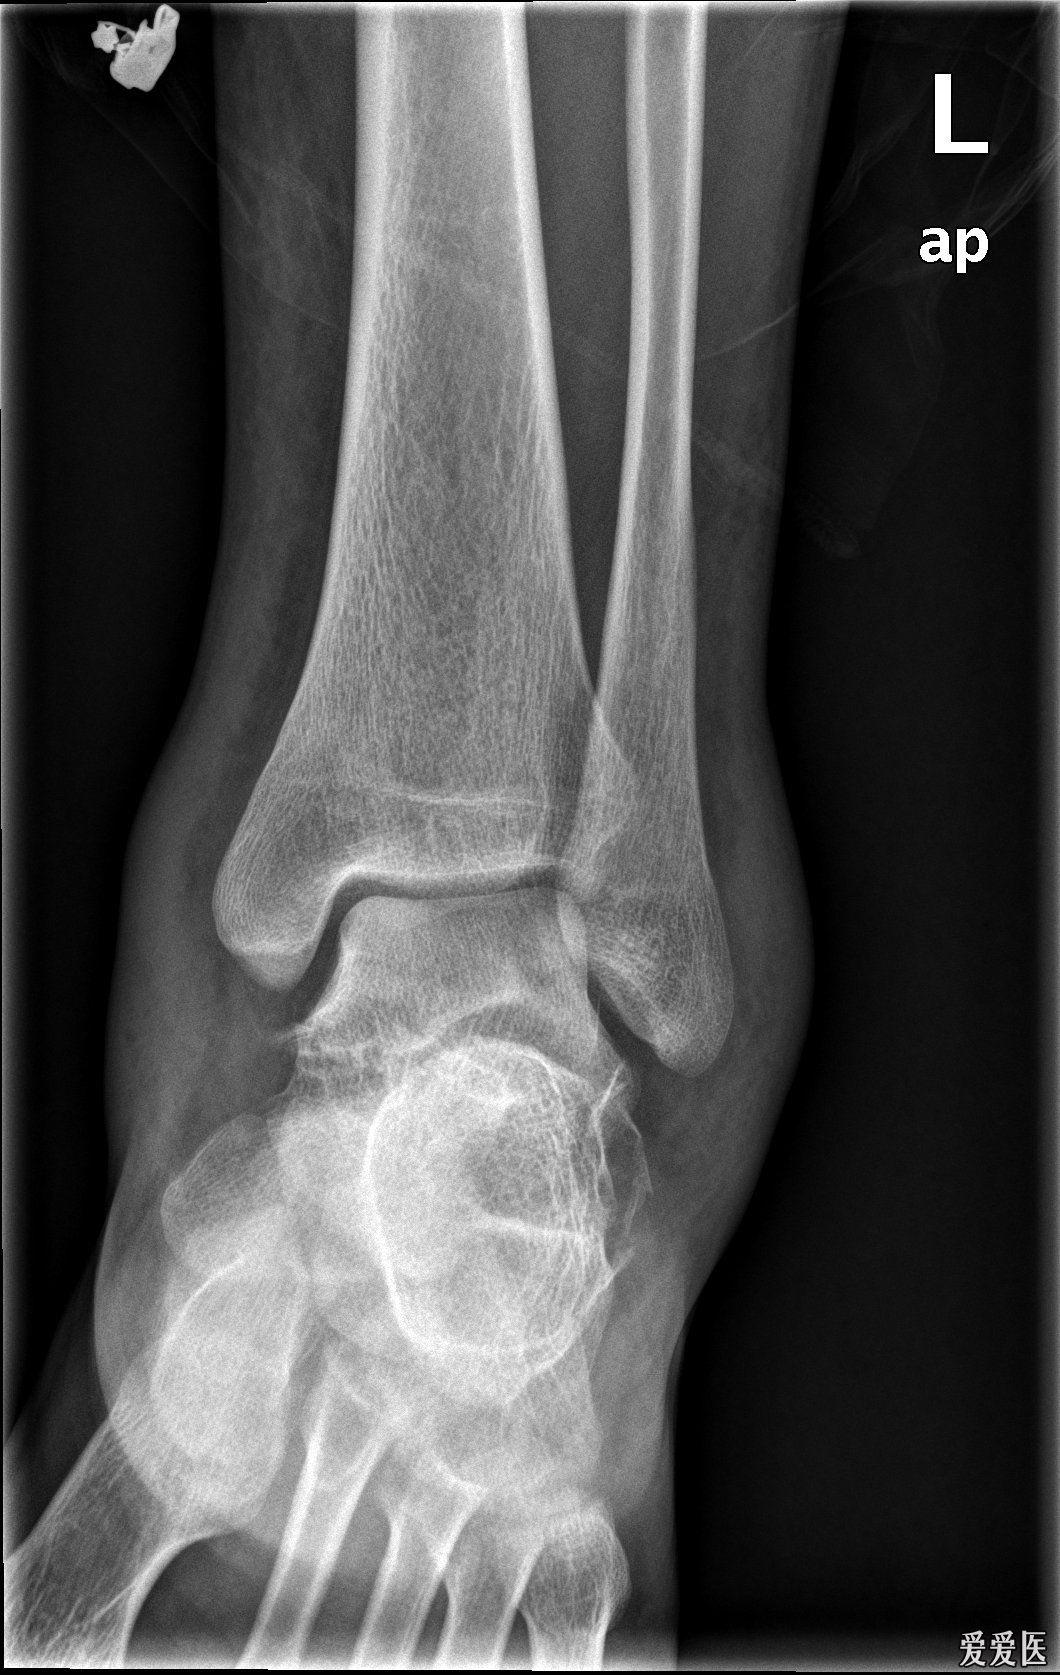

踝关节扭伤

甘肃省人民医院骨一科杨青山副主任医师团队:踝关节骨折

踝关节侧位x线片

踝关节创伤性关节炎